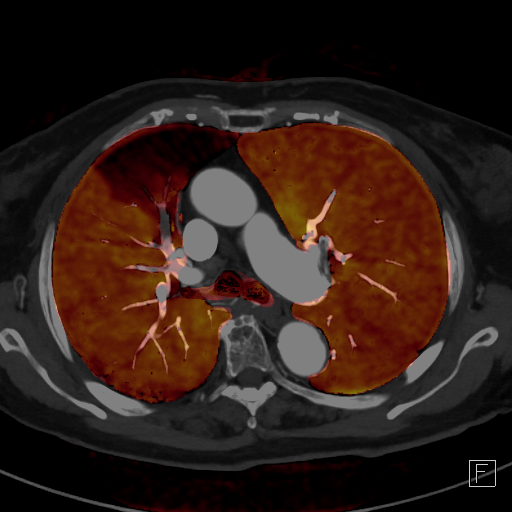

脱水や長時間同じ姿勢を取ることなどで脚の静脈の流れが悪くなり、血栓ができることがあります。その血栓が肺に運ばれて肺動脈を詰まらせてしまうのが肺血栓塞栓症です。CTを用いることで肺動脈内の血栓を造影欠損像として直接描出できます。さらに、デュアルエナジー撮影法を利用すると肺血流の機能情報を可視化することができます。

デュアルエナジーイメージングによる肺灌流評価CT(治療前と抗凝固薬服用後)